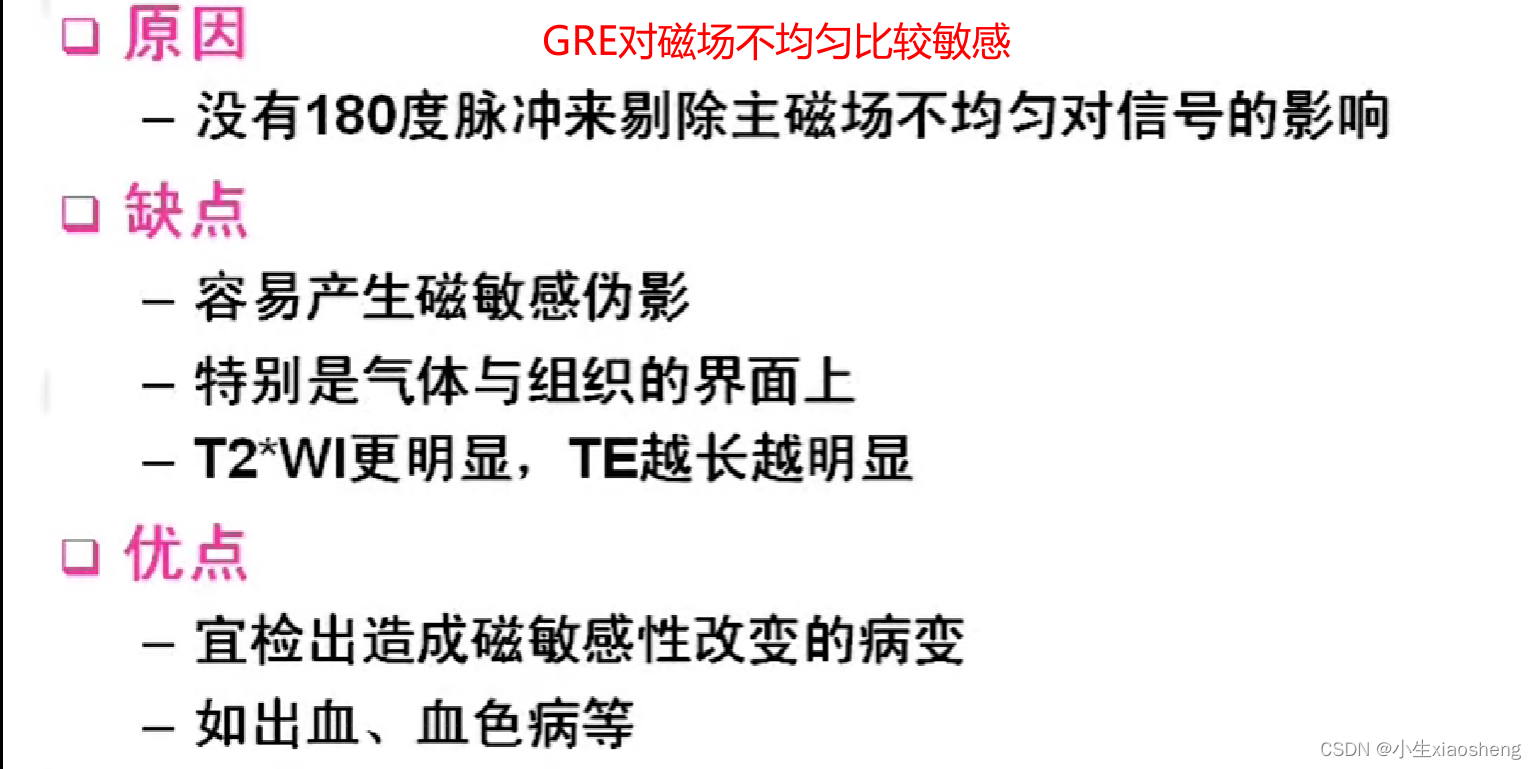

GRE就是梯度回波

GRE序列中的稳态:流入的和流出的量是一样的,那么容器中的数据一直都是一样的。